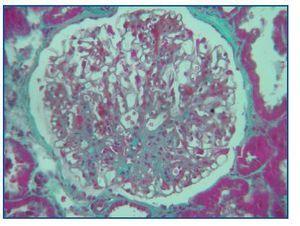

A bone marrow aspiration revealed hemophagocytosis with activated histiocytes (figure 1), normal hematopoiesis and no malignant cell invasion.

Histological examination at light microscopy showed sclerosis in 6 of the 9 glomeruli, modest mesangial proliferation, tubular atrophy and diffuse interstitial fibrosis (figure 2).

Figure 1.

Figure 2.